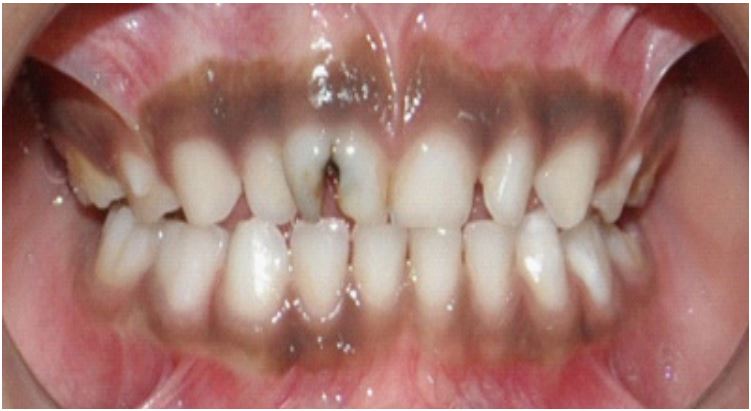

A 5-year-old male patient reported to our clinic with the chief complaint of decayed upper front teeth region. Patient presented with an episode of spontaneous pain which was relieved on medication. Medical history was non-contributory. Clinical examination revealed a geminated deciduous maxillary right central incisor (51, ISO system) having a large crown, showing a groove between non separated crowns on labial surface (Figure 1). It was noted to be non-vital on examination with electric pulp tester (Pulp tester C-pulse, Foshan CICADA Technology, China, input DC 9 V, output 80 V, 90 mA). Radiographic examination revealed two independent pulp chambers and two fused roots but with individual canals within (Figure 2). History, clinical and radiological findings pointed at the diagnosis of chronic irreversible pulpitis and pulpectomy was planned. Local anaesthesia (2% Lidocaine) was administered and rubber dam application was done. Access was achieved from the palatal surface and two canals were located; one, mesial and the other distal. Pulp extirpation and debridement was done by ProTaper Gold rotary files (Dentsply Maillefer, Ballaigues, Switzerland) upto F1. Irrigation of root canal was done with 2.5% sodium hypochlorite and saline. Obturation was done with Metapex (Meta Biomed Co. Ltd, Cheongju, Korea) (Figure 3). Access cavity was restored with glass ionomer cement till the cervical third and final restoration completed with composite.

Figure 3: Radiograph after pulpectomy.